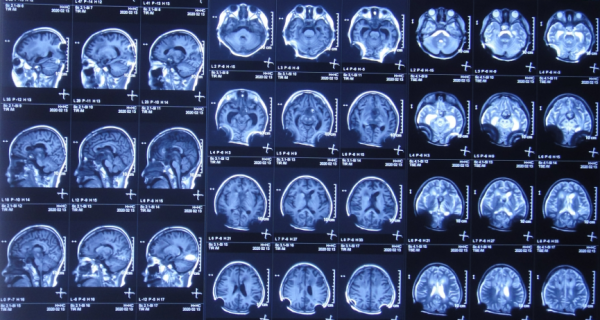

患兒於2019年12月5日下午,出現發熱,家屬自行給予口服布洛芬混懸液治療,但2019年12月6日凌晨2點左右,患兒睡眠中喊頭痛,家屬開車急送至安徽省蕪湖市弋磯山某三甲醫院,去醫院途中病情變重患兒呼之不應;到院後急診查頭部增強CT示蛛網膜下腔出血(圖-1),考慮血管畸形,於凌晨4點急診進行了腦室外引流術;術後當天早晨8點進行了DSA檢查排除血管畸形(圖-2)。

圖-1:2019年12月6日頭部增強CT